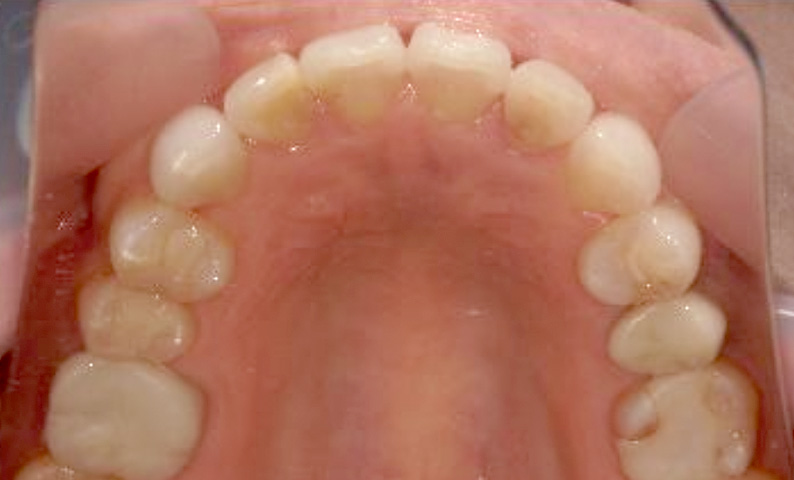

症例_002 上顎だけの部分矯正

治療期間:7ヶ月金額:30万円+税女性前歯のガタガタ上の前歯だけ

| Before | After |

|---|---|

|